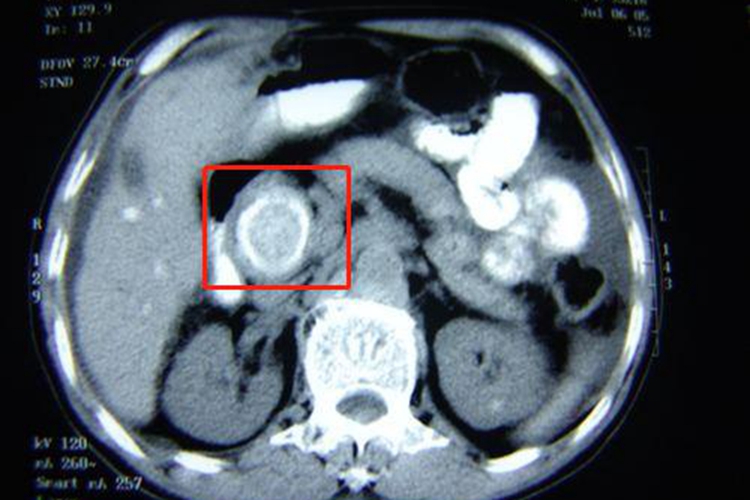

胆总管结石上部胆管扩张,CT表现为结石部位层面,可见圆形高密度结石周围环有低密度胆汁,构成“靶征”,若部分围绕,则形成“新月征”。